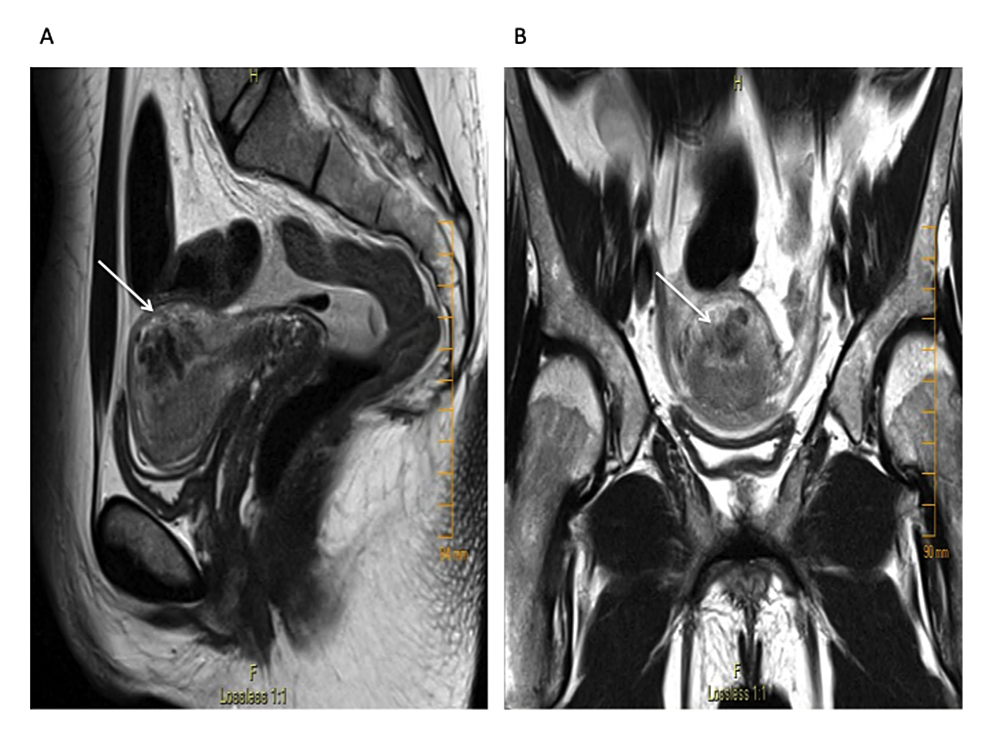

Transvaginal ultrasound revealed a 3.9 cm x 2.7 cm x. 1.8 cm sized anechogenic cystic space in the posterior wall of the fundus as seen in Figure 1, and with Doppler application, demonstrated marked vascularity (Figure 2). For further evaluation, pelvic magnetic resonance imaging (MRI) was performed, which revealed a contrast-opacified structure within the wall of the myometrium. Focal serpiginous flow voids were also noted within the posterosuperior myometrium with extension to the myometrial canal (Figure 3).